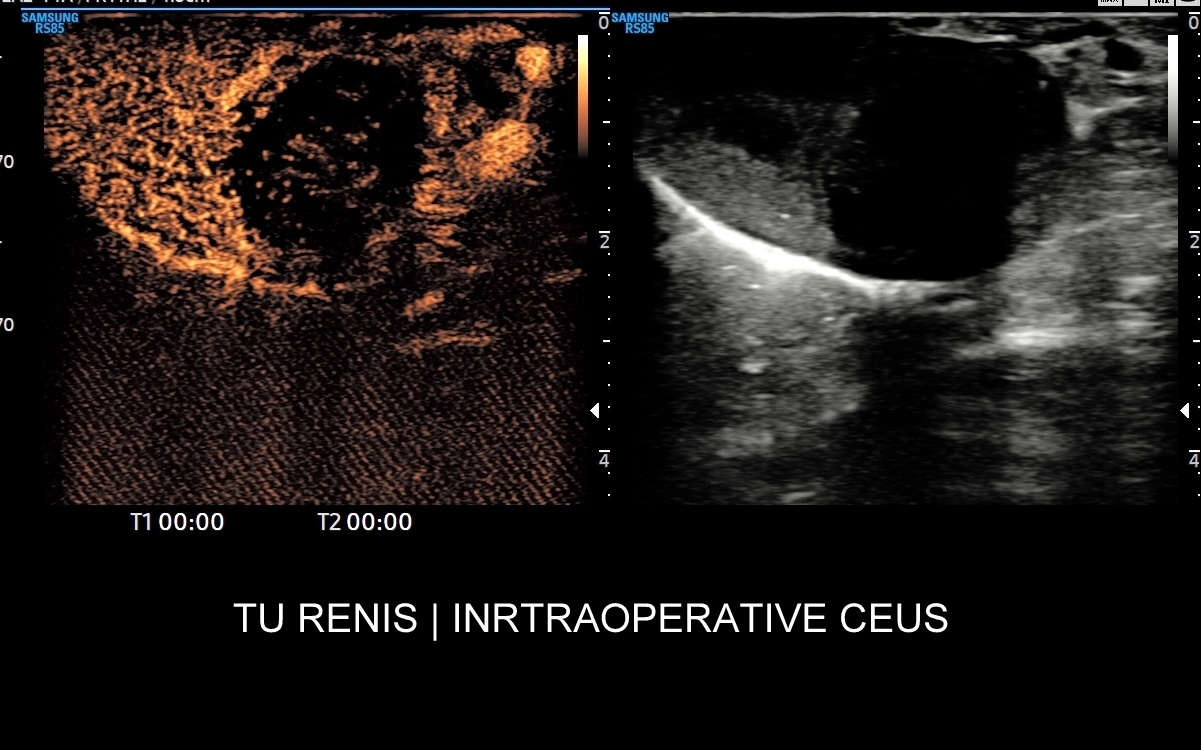

Badanie USG z kontrastem, nazywane również CEUS (ang. contrast enhenced ultrasound), jest nowoczesną metodą diagnostyczną wykorzystywaną w różnorodnych wskazaniach medycznych, w szczególności przy ocenie guzów i zmian ogniskowych narządów wewnętrznych takich jak wątroba, nerki, trzustka, drogi żółciowe, naczynia krwionośne, a także piersi i jądra. Badanie CEUS wykonają Państwo w Interdyscyplinarnej Pracowni Ultrasonograficznej prowadzonej przez dr Tomasza Szczepańskiego we Wrocławiu, pioniera ambulatoryjnych oraz szpitalnych zastosowań badań CEUS w Polsce.

Badanie USG z kontrastem, z języka angielskiego CEUS (contrast enhanced ultrasound), jest badaniem ultrasonograficznym, podczas którego, zwykle dożylnie, podaje się specjalny kontrast w celu uwidocznienia struktur narządowych oraz tkanek, które niewystarczająco wyraźnie są widoczne lub charakteryzowane w klasycznym badaniu USG, a nawet w innych badaniach obrazowych jak tomografia komputerowa (TK) czy rezonans magnetyczny (MRI).

Narządem, w którego diagnostyce najczęściej wykorzystuje się CEUS, jest wątroba; w dalszej kolejności nerki, trzustka, protezy naczyniowe aorty, drogi żółciowe oraz inne narządy wewnętrzne.